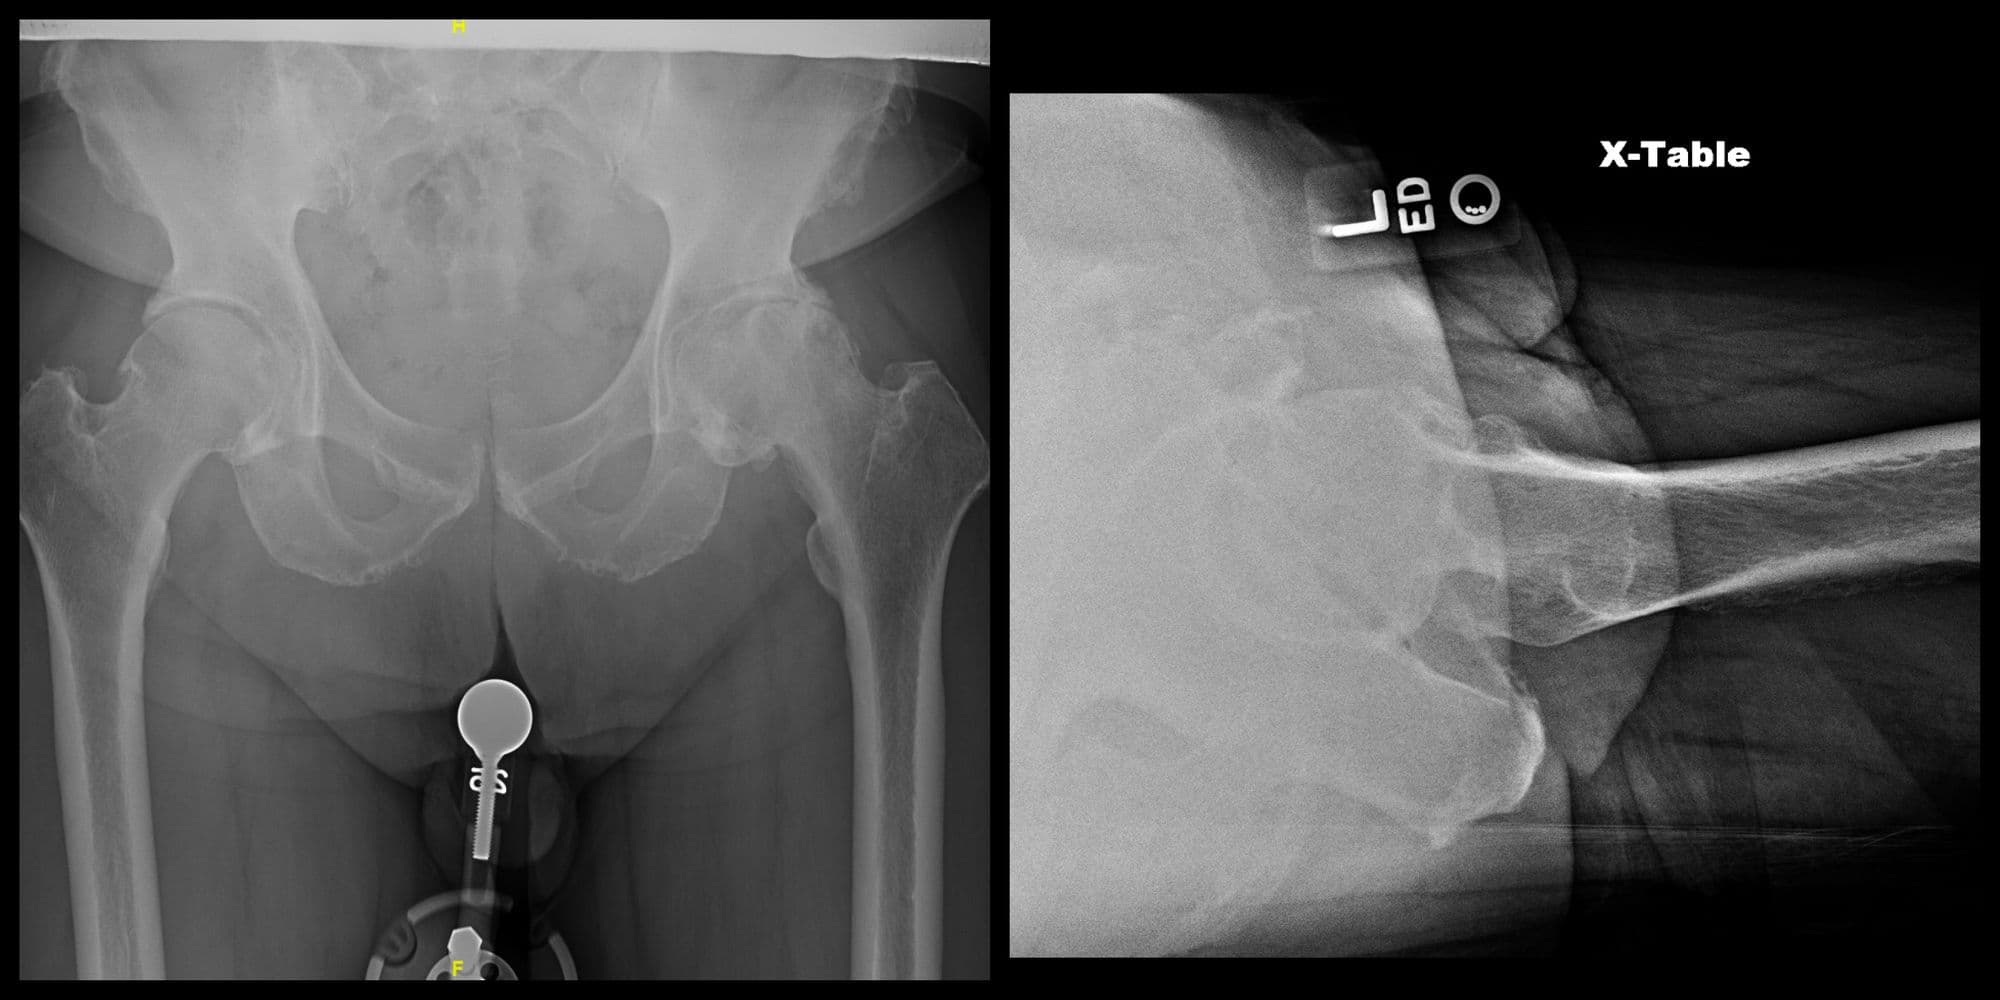

Imaging

Pre-op